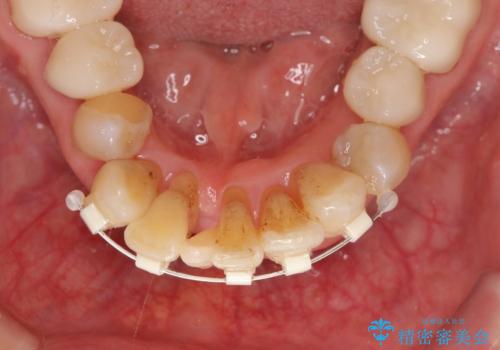

- 上顎前歯の黒ずみの改善、下顎前歯の十度なガタつき、矯正治療とセラミック治療を含む全体的な治療を希望され来院されました。

銀歯を高強度の仮歯に替えたのち、下顎前歯のみの部分矯正→全体的なマウスピース矯正治療(インビザライン)→最終的なセラミック治療と治療を進めます。

矯正治療と目立つ銀歯のやりかえを行ったことでかみあわせだけでなく、審美性・清掃性も改善し口腔内の環境を劇的に改善することができました。